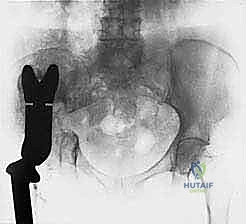

- Plain Radiography (FIG 2): While of limited value for early lesions, it provides an initial overview. As you can see in Figure 2A, we have a large lytic lesion of the right periacetabular region. Figure 2C shows a cartilage-forming lesion in the left ilium. However, plain films often underestimate the true extent of these tumors.

* CT with Intravenous Contrast and 3D Reconstruction (FIG 3): This is our workhorse for assessing bone involvement, destruction, and the critical relationship between the tumor and major pelvic blood vessels. It reveals any distortion of the pelvic anatomy and guides resectability. Figure 3A clearly shows extensive bone destruction and tumor extension into the pelvis and gluteal region. Figure 3C highlights an extensive tumor on the medial aspect of the ilium with destruction of the inner table.

- Initial Cuts: "We'll start with the iliac wing osteotomy. Use a large oscillating saw or Gigli saw, under constant visual and fluoroscopic guidance, to make the superior cut through the ilium, staying well clear of the sacroiliac joint."

* Acetabular Cuts: "Next, we'll address the periacetabular cuts. This requires careful planning to maintain stability for reconstruction. We'll use a combination of osteotomes and a small oscillating saw. The pubic ramus will be cut anteriorly, and the ischium posteriorly. Ensure adequate bone stock for reconstruction."